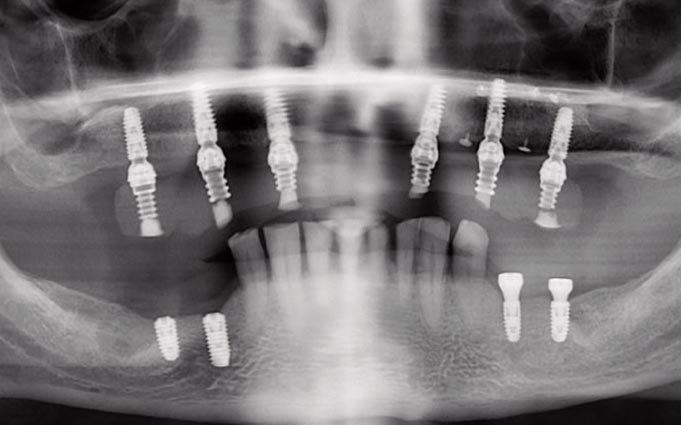

Стоматологические Исследования: Рентген Инвагинации Зубов